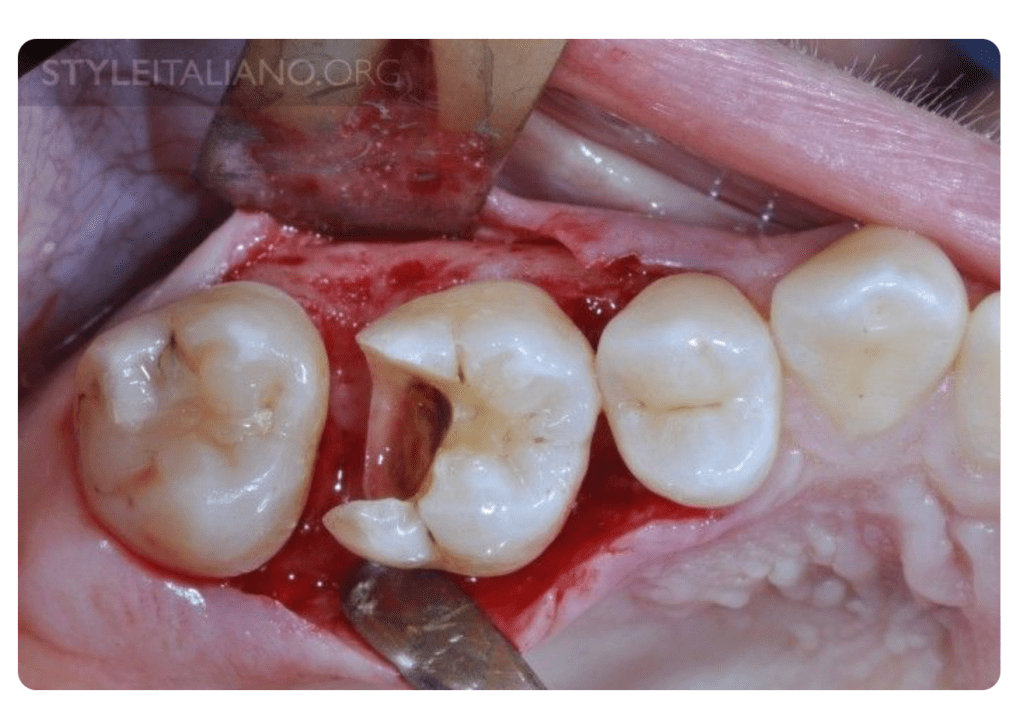

✅ 1. 蛀牙蛀太深,已經到牙齦下方

牙醫師在修補時看不到邊界、無法清乾淨,硬補只會造成二次蛀牙。

🦷 牙冠增長術到底在做什麼?

是把牙齦或少量骨頭往下修磨整理,讓更多健康的牙齒露出來。

3. 🔸 修磨整理牙齦與周圍骨頭高度,符合生物寬度與假牙製備原則

4. 🔸 讓牙齒露出足夠齒質